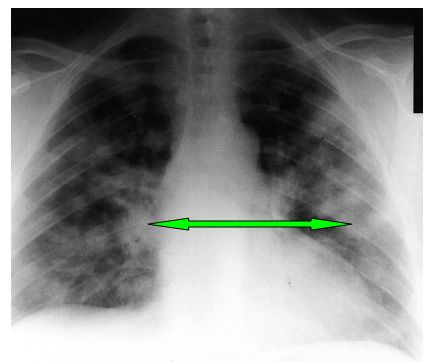

Figure 1.

Arrows indicate bilateral infiltrates.

The patient was pale and had small telangiectasias on his face. He had mild tenderness over the knees and shoulders. Active and passive range of motion measures were normal. Results of blood chemistry tests were: sodium, 135 mEq/L; potassium, 5.3 mEq/L; chloride, 107 mEq/L; bicarbonate, 15 mEq/L; BUN, 91 mg/dL; creatinine, 7.9 mg/dL; glucose, 81 mg/dL. The hemoglobin level was 8.4 g/dL; white blood cell (WBC) count, 10.9 x 103/μL; platelets, 234 x 103/μL. Urinalysis revealed large amounts of blood, and 82 red blood cells (RBCs) per high-power field. Chest films revealed bilateral infiltrates (Figure 1).